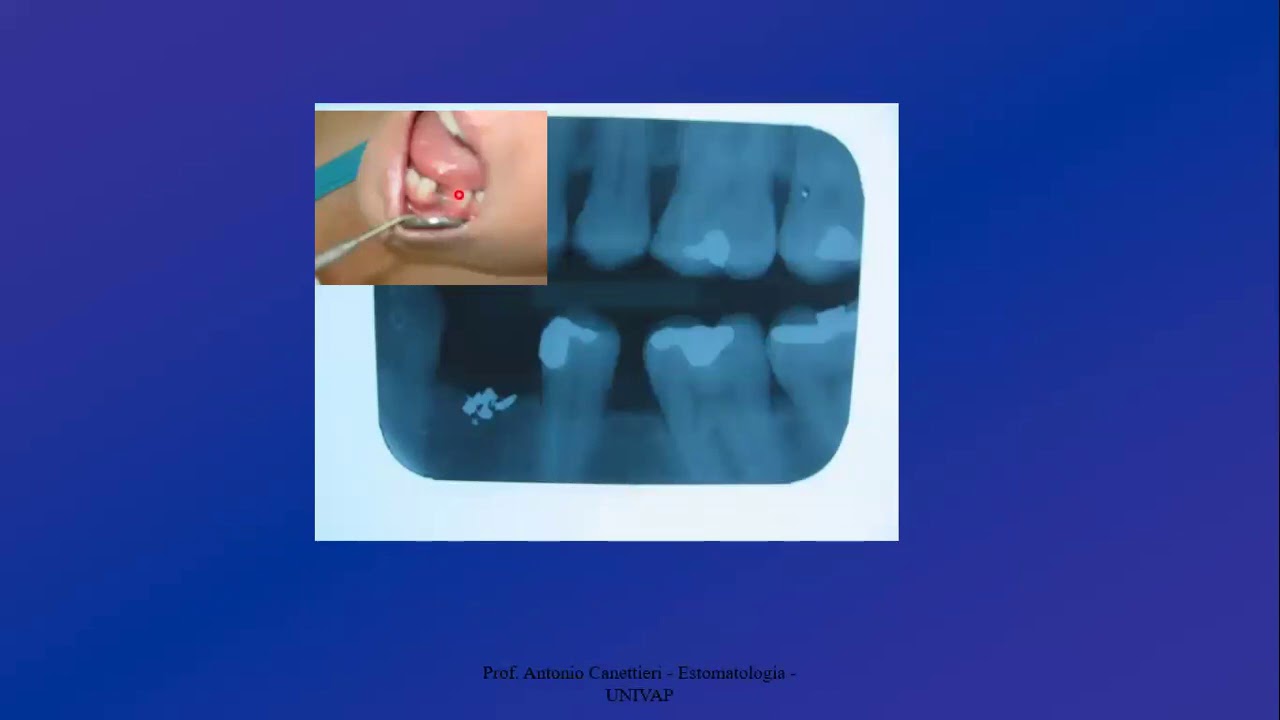

falar separadamente vou fazer um vídeo falando sobre o pente um vídeo falando sobre herpes um vídeo falando sobre mucocele enfim mas eu quero saber de você se você é Acho interessante esse assunto deixa aqui nos comentários falando Bruno Faz sim essa playlist que eu vou gostar eu vou assistir eu vou mandar para o meus amigos que eu faço para eu saber se vocês querem esse tipo de conteúdo mas agora sem mais enrolação chegou a hora da nossa pergunta daquele projeto que o início do vídeo A pergunta é a seguinte essa lesão que tá aparecendo aqui

ela apresenta a base Sérgio ou pediculada ele vai lá no Instagram depois que acabar esse vídeo Responde lá na dma Bruno ela apresenta base e tal e aí se você acertar a resposta resposta ver certinho eu vou mandar para você um link que você vai baixar o mapa mental dos assuntos referentes a esse vídeo de hoje beleza e toda semana vai ter um vídeo novo com perguntas novas com mapas mentais novos totalmente gratuito para você baixar show e se você gostou desse vídeo eu quero fazer alguns pedidos aqui para você tá primeiramente não esquece de